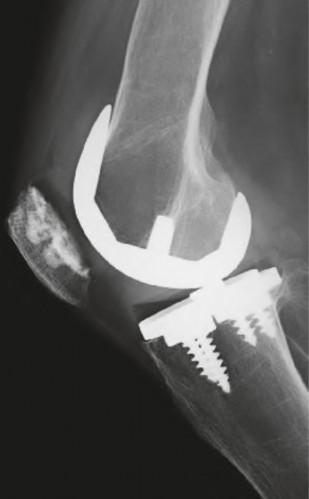

A 60-year-old male tennis player undergoes a unicompartmental knee arthroplasty (UKA) shown in Figures A and B. Which of the following statements regarding this procedure is true?

Figures A and B depict radiographs of a unicompartmental knee arthroplasty (UKA). UKA kinematics have been shown to most closely approximate native knee kinematics.

In an in vitro cadaver study, Patil et al found that TKA significantly changed knee kinematics while the unicompartmental replacement preserved normal knee kinematics.

Fisher et al performed a retrospective study comparing the short-term outcomes of small-incision unicompartmental knee arthroplasty (UKA) with standard total knee arthroplasty (TKA) in 91 consecutive patients older than 70 years. They found: 1) Blood loss was significantly more for the TKA group, as was the need for blood transfusion. 2) Patients with unicompartmental replacements had a much quicker return of function and discontinuation of pain medication. 3) While knee scores and ROM were similar preoperatively, both were better in the unicompartmental group at each postoperative time interval. 4) Narcotic use and length of hospital stay were also significantly less for the unicompartmental group. Therefore answers 2,3,4 and 5 are false.